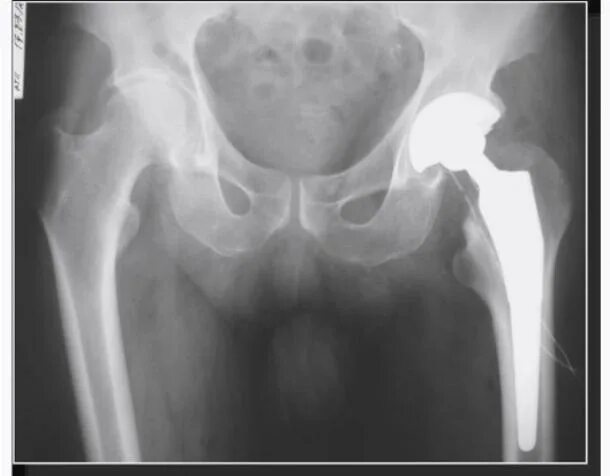

Коксартроз тазобедренного 3 степени группа инвалидности